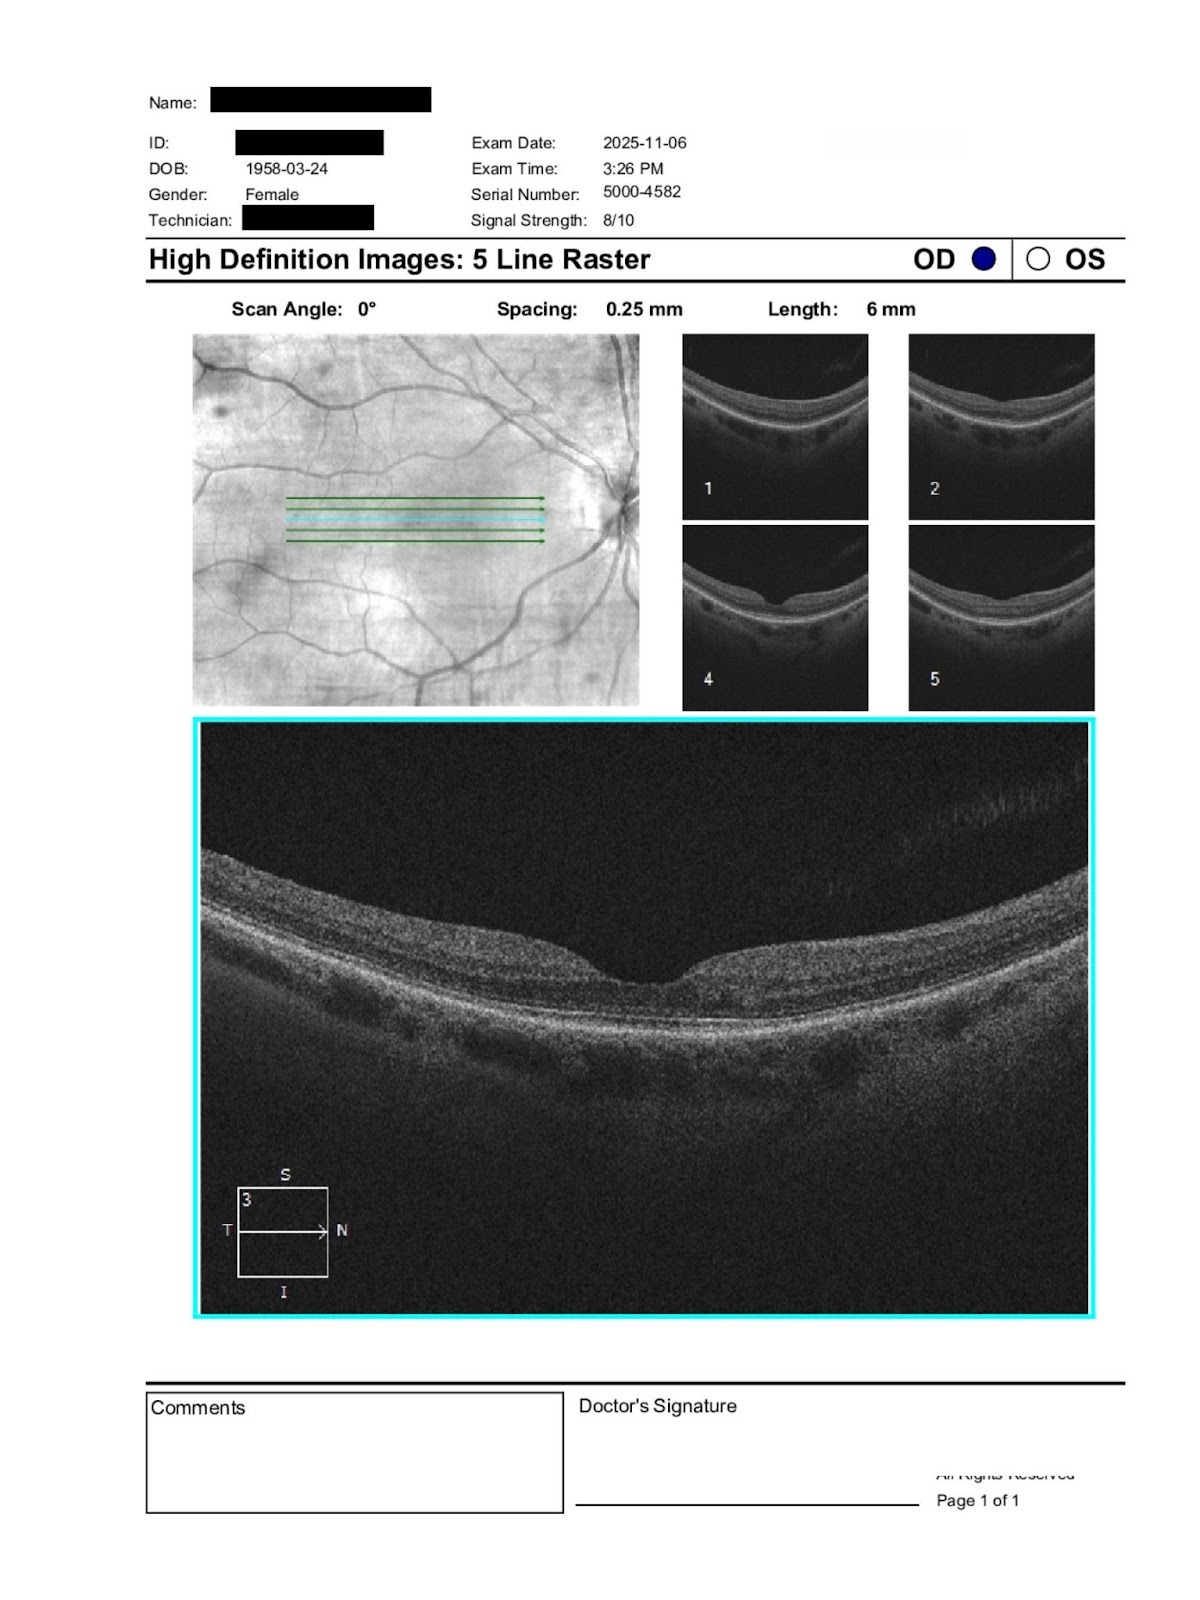

A 67-year-old female with reduced BCVA OD, mild cataract changes, and foveal irregularity; history of lupus and prior plaquenil exposure.

67-year-old female with reduced OD vision. History: prior plaquenil use, lupus, anemia, AFib, arthritis. Medications: Ezetimibe, Prednisone, Apixaban, Metoprolol.

VA: 20/50 OD → 20/40 OD with refraction; 20/40 OS → 20/25– OS. IOP: 18 OD / 15 OS. Exam: mild nuclear sclerosis OU, central posterior opacity OD, tear breakup 3 sec OU (dry eye, CPAP use). Posterior: healthy discs, OD macula foveal irregularity, OS macula flat; periphery clear.

Question: With mild cataract and OD macular changes, what is the relative lenticular vs macular contribution, and is further retinal imaging/referral warranted?

The reduced best corrected acuity in the right eye appears multifactorial. A small central posterior lens opacity may contribute to decreased contrast and acuity, particularly under mesopic conditions. However, the documented foveal irregularity raises concern for subtle macular structural change.

Given the history of prior hydroxychloroquine use and autoimmune disease, careful OCT review of the ellipsoid zone and parafoveal outer retina is recommended to rule out early or residual toxic maculopathy.

If OCT demonstrates disruption of outer retinal layers or progressive change, in person retinal evaluation is appropriate. If imaging is stable and lens opacity correlates with symptoms, cataract progression may be the primary contributor. Close follow up is advised to monitor for progression.

When reduced acuity does not fully correlate with refractive error or lens findings, subtle macular pathology should be suspected. Foveal contour irregularities may reflect prior inflammatory, toxic, or degenerative changes and can limit visual potential even in the absence of obvious edema or hemorrhage. Optical coherence tomography is essential in distinguishing photoreceptor layer disruption from surface or lenticular causes of blur.

Hydroxychloroquine retinal toxicity preferentially affects the parafoveal photoreceptors in early stages and may remain detectable on OCT even after medication cessation. Structural changes in the ellipsoid zone often precede visible fundus findings or marked visual acuity decline.